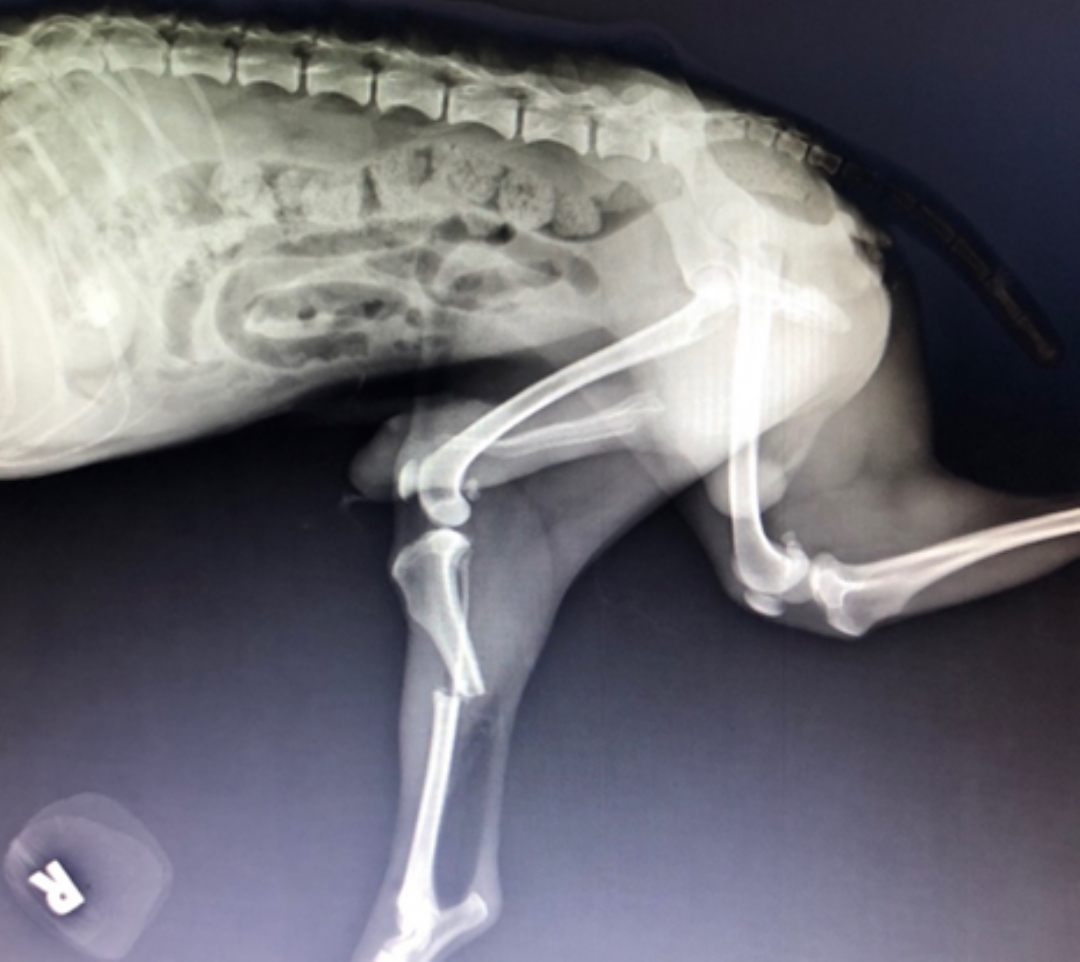

犬貓常因高處墜落、外力撞擊或車禍等原因造成骨折,常見部位包括下顎骨、四肢骨骼和骨盆。骨折需透過X光初步評估,若為複雜骨折則需進一步進行電腦斷層掃描。根據骨折位置和程度,醫師會選擇適合的植入物如骨板、鋼釘等進行修復,並搭配外固定包紮與限制運動。術後通常可望恢復正常活動,預後良好。

犬貓常因高處墜落、外力撞擊、車禍等原因導致骨折例如下顎骨、

四肢骨骼、骨盆等等多處的骨骼骨折,骨折須藉由x光來初步評估骨折位置和形式及制定手術方式,

但當面對複雜性骨折時就需要進一步掃電腦斷層來進一步評估手術,骨折修復手術會考量到動物的體型、

骨折位置和形式及軟組織傷害的程度來評估選擇的植入物(例如:骨板、骨釘、鋼線、螺絲),

經手術治療骨折優點在於提供患處部分支撐及增加骨折斷片固定度,

術後需搭配外固定包紮並且限制運動,通常預後都不錯可以恢復到原本蹦蹦跳跳的樣子。

粗分為簡單或複雜性骨折,以下有許多骨折修復手術病例分享: